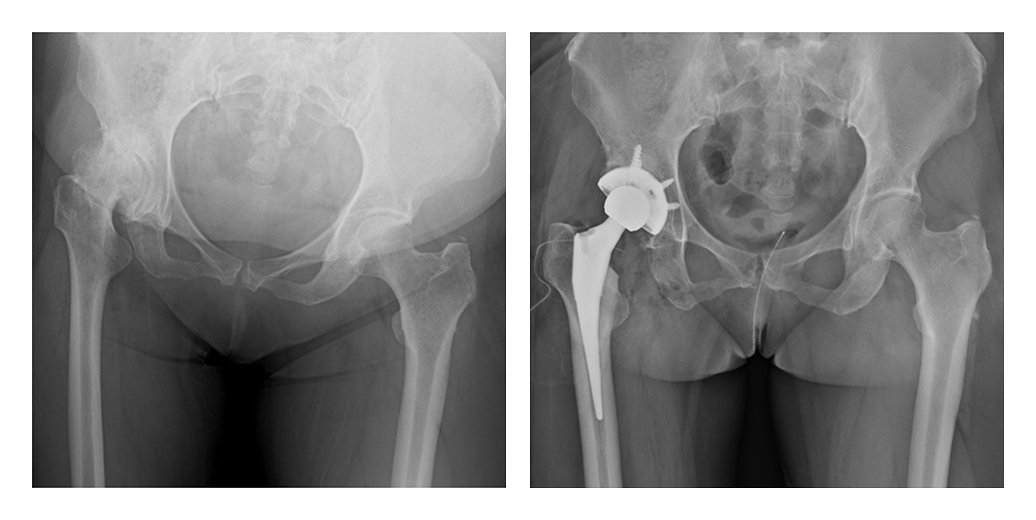

変形性股関節症とは股関節の軟骨がすり減ることにより発生する関節の痛みと機能障害です。原因の多くは子どもの時からの発育性股関節形成不全が原因ですが、高齢社会の影響で年齢とともに骨質が悪くなることにより急激に股関節症が進行してくることも増えています。(日本整形外科学会「変形性股関節症」)

当院では、変形性股関節症や大腿骨頚部骨折、大腿骨頭壊死症などに対し、最先端の人工股関節置換術(THA)を行っています。手術技術の進歩による低侵襲手術、人工股関節のインプラント部品の進化による長期耐久性が実現したことで高齢者から比較的若年の方まで手術適応が拡大し、手術患者数は年々増加しております。

私たちの強みは、症例に応じてセメント固定型・セメントレス固定型を適切に使い分けることです。

骨質がしっかりした方には、骨と人工関節が自然に結合するセメントレスTHAを。骨粗鬆症を伴う高齢の方や骨折例には、早期に安定した固定が得られるセメントTHAを選択。どちらも豊富な経験をもとに、安全性と長期耐久性の両立を目指しています。

また、手術は患者様の体にできるだけ負担をかけない低侵襲(MIS)アプローチを採用しています。術前3Dテンプレート計画や簡易ナビゲーションシステムなどの先端技術を活用し、脚長差や可動域のバランスにも細心の注意を払います。